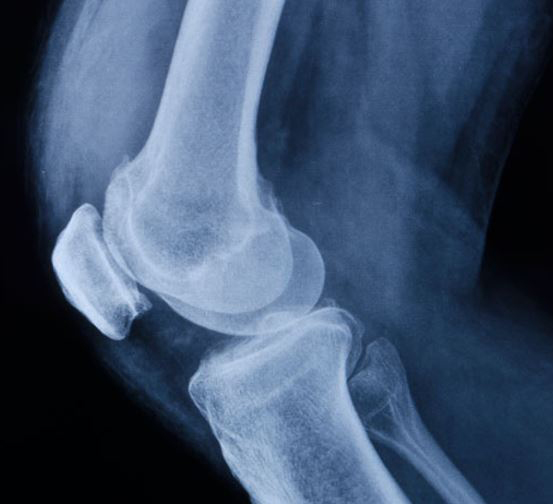

Chronische Schmerzerkrankungen der Wirbelsäule und der Bewegungsorgane Degenerativ-rheumatische Erkrankungen

- Arthrose (Gelenkverschleiß)

Nach Operationen, Unfallfolgen und Sportverletzungen am Bewegungsapparat

- Endoprothesen (Hüfte, Knie, Schulter, Sprunggelenk, Wirbelsäule) Osteoporose